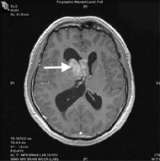

This MRI shows complete removal of the tumor

The port tract (arrow) is visible on the MRI taken in the Intra-Operative MRI Suite. This MRI shows complete removal of the tumor.